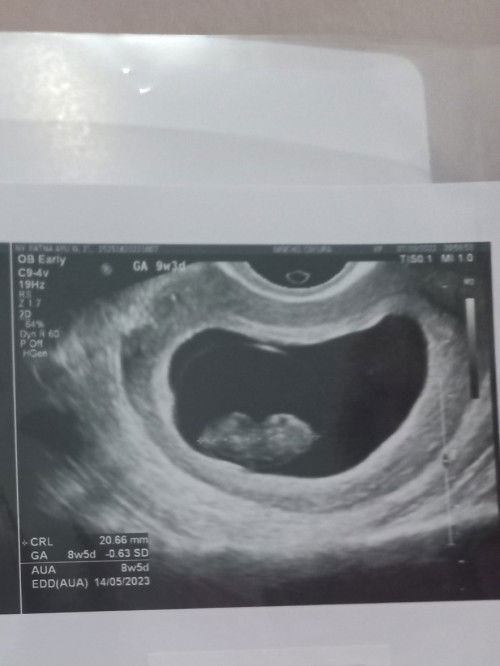

Baca lagisaya waktu usg 9w djj nya juga masih lemah bun kata dokternya, bahkan saya mikirnya mlah belum ada djj nya soalnya pas di usg cuma kedengeran suara bising saja.. saya gak ada keluham kram/nyeri perut/flek.. tp dokter bilang baik2 saja suruh balik lg 6minggu lg gitu.. kemarin pas 13w udah priksa lagi Alhamdulillah djj nya udah lebih kenceng udah kedengeran... semangatt bunda 🥰

sama bun mnrut hpht 10 w tp di usg 8w dn blm trdngr djj. dsruh balik kontrol 2 mnggu lg. dikasih obt penguat juga, soalnya aku kluar flek sdkit bun dn itu pun kluarnya cuma skali yg gk terus2an gt

smaa bunda aku juga alamin hal yg sama 9w djj blm ad padahal janin sdh ad , tapi minta tunggu 2 minggu kontrol lagi semoga djj sdh ada aamiin , semangat yaa bunda kita berjuang sama2

Sama bun aku malahan seharusnya 12w tp pas hasil usg 8w dan blm ada djj juga 🥹🥲